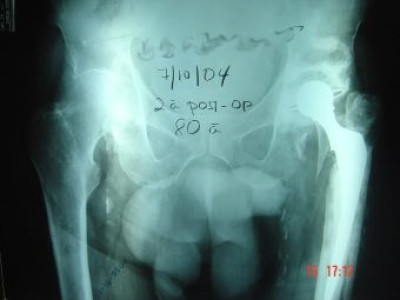

Prótesis Total de Cadera por Fractura

Envíado por Dr. Ricardo Antonio Gómez G.